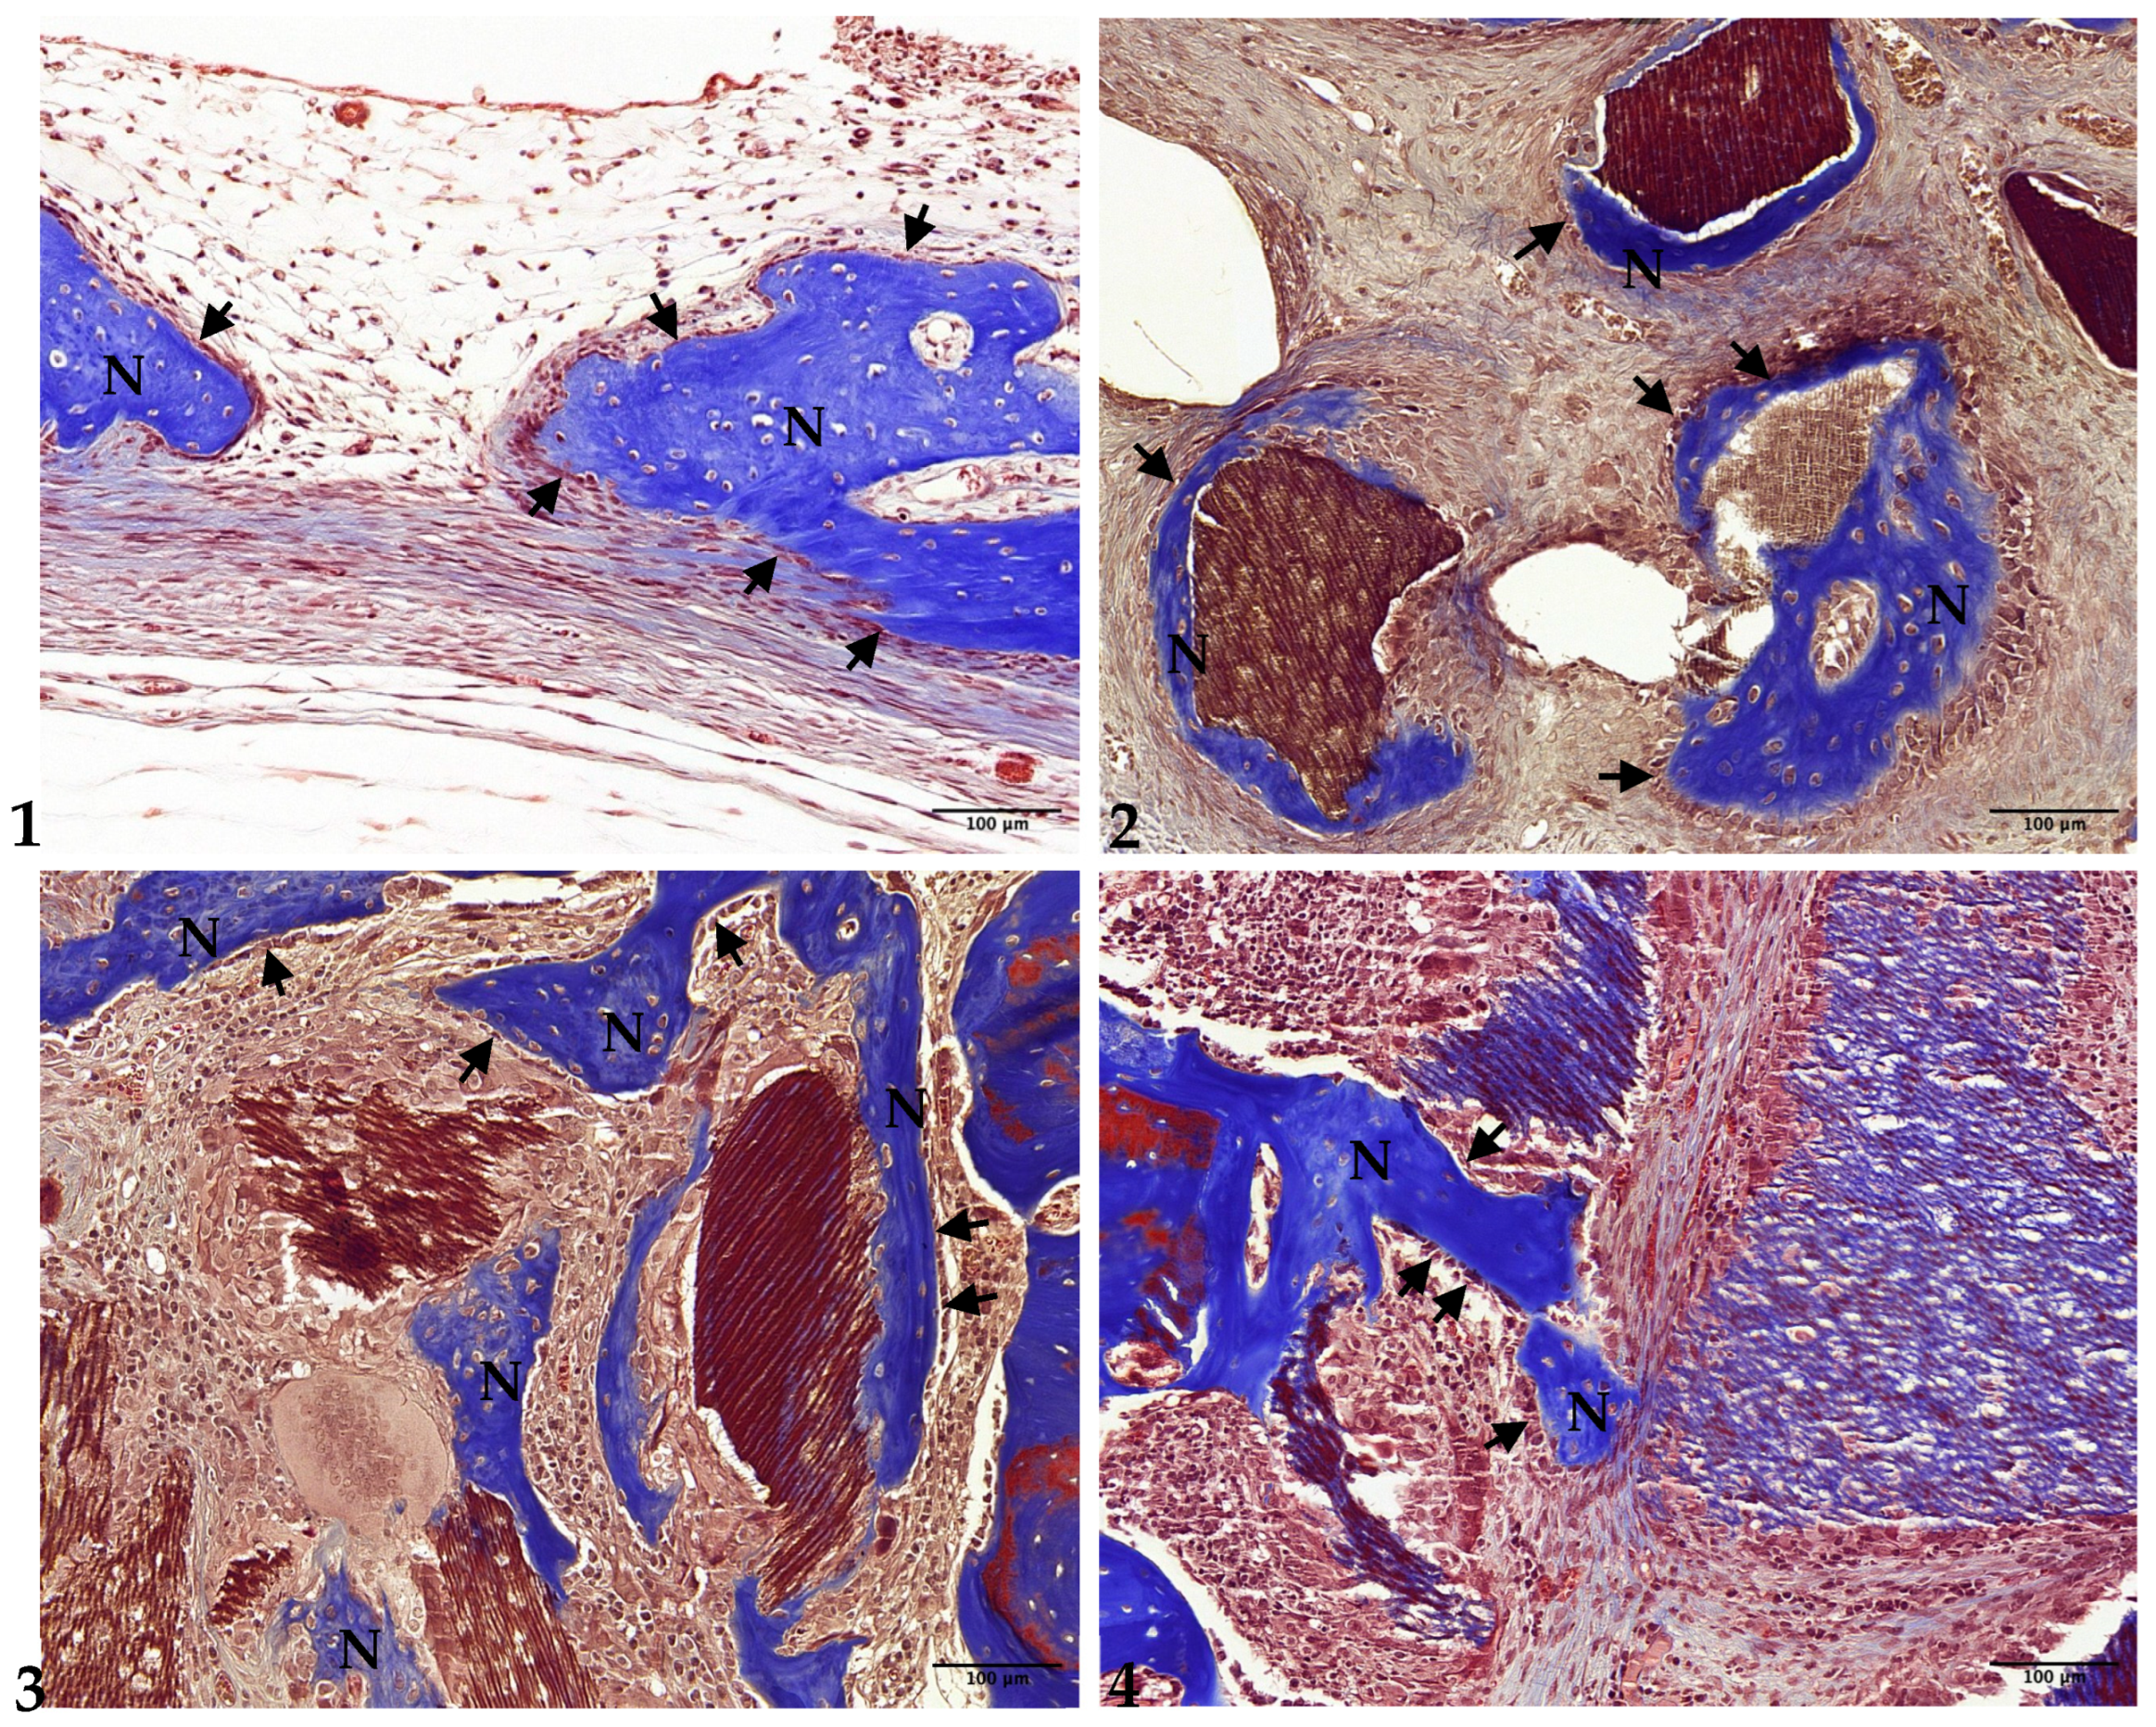

3.1. Histological Analysis

3.2. Two-Week Results

3.3. Four-Week Results

3.4. Eight-Week Results